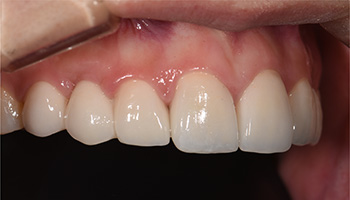

前歯部オールセラミック症例

治療後

保険のかぶせ物とつめ物だと年数がたってくると変色したりしてしまいます。また、保険のかぶせ物は中に金属を用いているため、歯ぐきも黒く見えてしまいます。それを金属を使わないオールセラミッククラウンを用いることで透明感のある自然な歯に仕上げることができ、変色もありません。